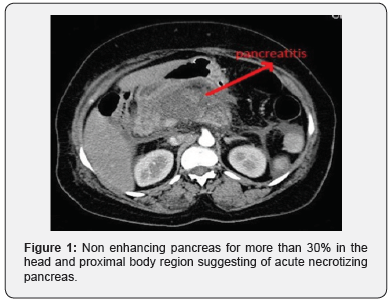

Initial investigations revealed serum amylase 956 IU/L. Her liver enzymes, serum calcium, triglyceride levels were within normal limits. Abdominal ultrasound revealed minimal free fluid abdomen. Pancreas was obscured by bowel gas, gall bladder and common bile duct were normal. CT abdomen demonstrated diffusely enlarged pancreas with shaggy contour and non- enhancing pancreas for more than 30% in the head and proximal body region (Figure 1). Modified CT Severity Index (CTSI) was 8, suggestive of Acute severe Pancreatitis. There was part of the head noted on the right of the second part of duodenum which was continuous with the rest of the pancreas suggestive of Annular Pancreas (Figure 2). The third part of the duodenum was seen anterior to the superior mesenteric artery and transverse colon found to be behind the SMA (Figure 3). The hepatic flexure, ascending colon and caecum were seen in the right iliac fossa due to non fixation, consistent with reverse rotation of the intestine (Figure 4). There were no signs suggestive of pancreatic infection.

Pancreatitis due to annular pancreas generally involves the annulus and the adjoining pancreatic head, preserving the body and tail of the gland [12]. This is probably attributed to inability of pancreatic secretions to flow through the Santorini duct, where as the main pancreatic duct allows the flow of secretions from the body and tail of the pancreas to remain intact [13]. This patient had 30% necrosis of head and proximal body which corresponds to the above explanation.